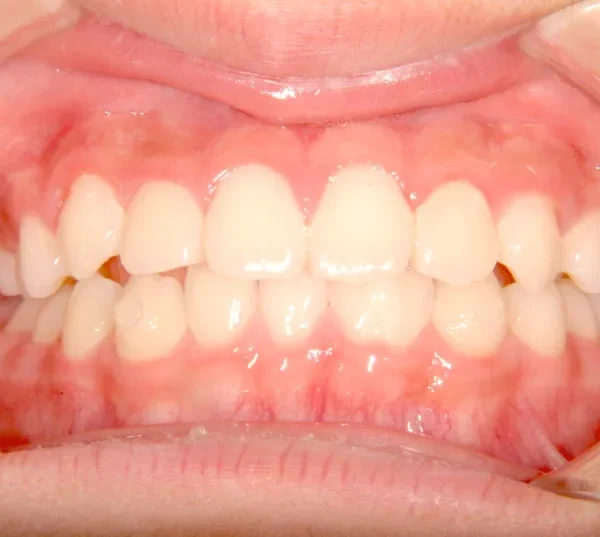

治療終了後

オリジナルの着け外しのできる装置で治療しました。

治療回数○回、4年7ヶ月の治療期間で矯正治療を終了しました。

1期治療で十分な結果が得られたと思います。